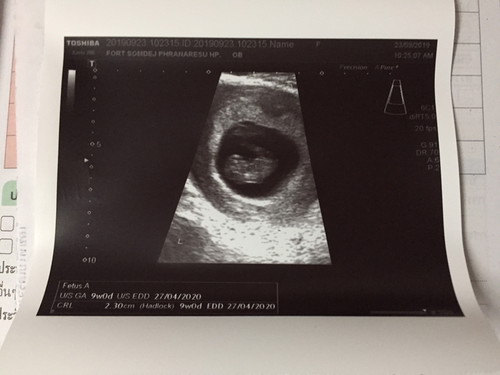

ท้องแรกค่ะ 9w แล้ว ตื่นเต้นหน่อยๆ??? วันนี้ไปฝากท้องกับคุณหมอมาค่ะ คุณแม่แพ้ทานไรไม่ได้เลย น้ำหนักก่อนท้อง 68 วันนี้ไปชั่งมาเหลือ 61 แต่คุณหมอบอกน้องแข็งแรงหัวใจเต้นดีค่ะ เมื่อไหร่จะหายแพ้ไม่รู้??